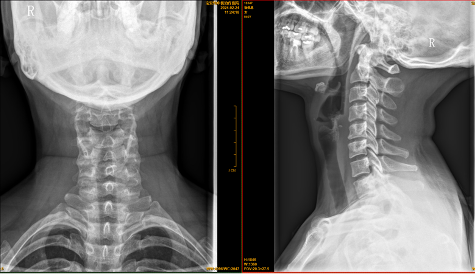

【影像】 颈椎X线片见颈椎平直,向右侧弯,C5-6椎间隙狭窄,椎体后缘骨质增生。C5-6、C6-7右侧椎间孔狭窄。右侧寰枢外侧关节对合不全,左侧显示不清,枢椎棘突偏左。

【讨论】本案症见右上臂酸痛无力、时有手指麻木,查体项僵、右椎间孔挤压试验(+)、颈椎右旋右上肢麻木,X线见颈椎平直、向右侧弯、C5-7右侧椎间孔狭窄,诊断为颈椎病。针灸治疗后症状减轻,貌似诊疗无误,实则不然。

患者右上臂酸痛无力、劳累右侧肩部酸痛、右侧卧位右上肢麻木可用颈椎病解释,与X线所见不冲突。而右手尺侧三指麻木为C7、C8神经根受压所致,X线仅见C5-6、C6-7右侧椎间孔狭窄,无法解释C8神经根受压。

右侧风池穴压痛(+)、右侧头后大直肌紧张压痛(+),X线片见右侧寰枢外侧关节对合不全、左侧显示不清、枢椎棘突偏左,考虑“寰枢关节紊乱”。患者没有颈枕部疼痛、旋转受限、头晕、头痛、失眠等相应症状,不能下 “寰枢关节紊乱综合征” 的临床诊断。